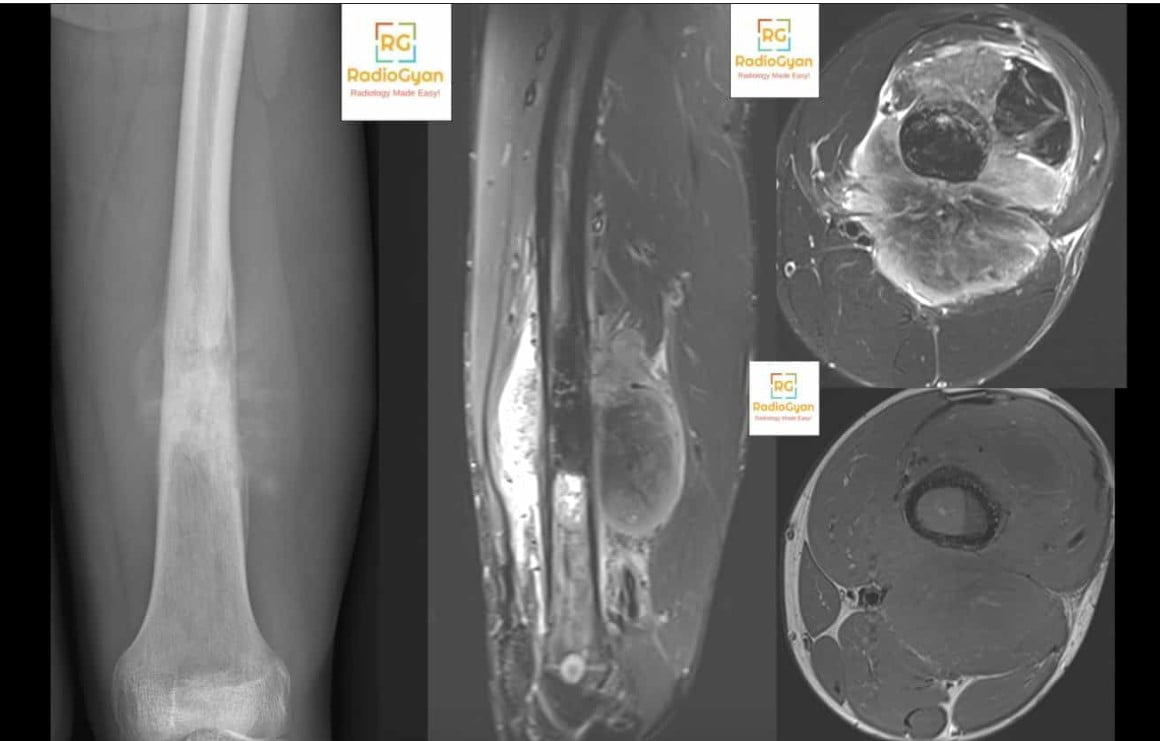

Sunburst periosteal reaction is caused by an aggressive periosteal response to rapidly growing bone lesions, including malignant primary bone tumors such as osteosarcoma, metastatic bone disease, or aggressive infections. It is also seen in other aggressive bone conditions like Ewing sarcoma, haemangioma, plasmacytoma, and tuberculosis. This reaction indicates rapid new bone formation in response to cortical destruction or irritation.

The term sunburst refers to the radiographic appearance where new bone spicules radiate outward in a divergent, ray-like pattern from the cortex, resembling rays of the sun emanating from a center point. This X-ray pattern is a key imaging modality indicator of aggressive periosteal bone formation.

The sunburst periosteal reaction pattern occurs when the periosteum attempts rapid formation of new woven bone in response to a rapidly expanding lesion. Because the process is aggressive and rapid, the periosteum cannot lay down a continuous or organized lamellar bone layer. Instead, multiple spicules of bone form perpendicularly and diverge outward in a disorganized fashion, producing radiating linear opacities on radiographic imaging. This represents aggressive periosteal bone formation induced by an underlying rapidly growing tumor or infection.